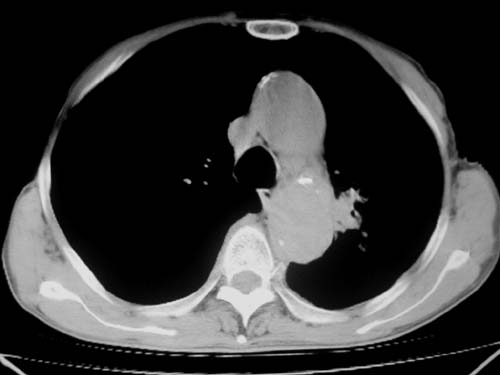

标题: CT19736:男,76岁,咳嗽,胸痛 [打印本页]

标题: CT19736:男,76岁,咳嗽,胸痛

支持左上肺周围型肺癌性并空洞形成伴胸椎转移。

左上沟癌空洞形成并胸椎转移。

支持 左上肺周围型肺癌性并癌性空洞形成伴胸椎转移。

考虑癌性空洞并胸椎转移。

空洞内壁有多发结节,支持癌性空洞。